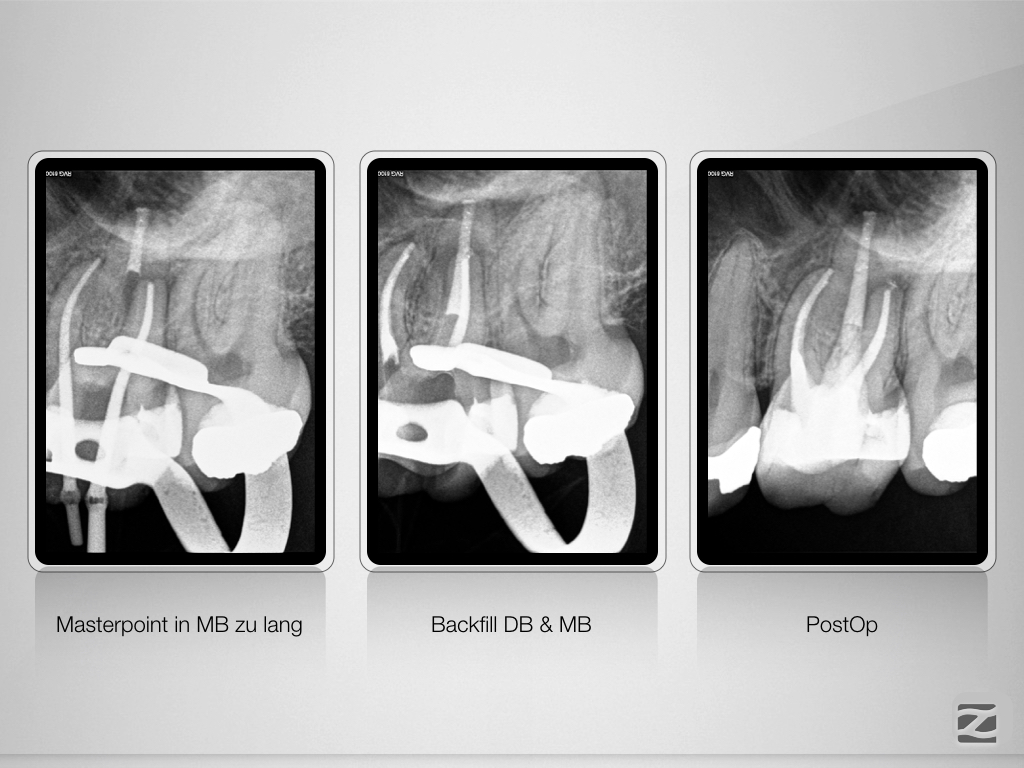

26D.010

Eene, meene, muh …